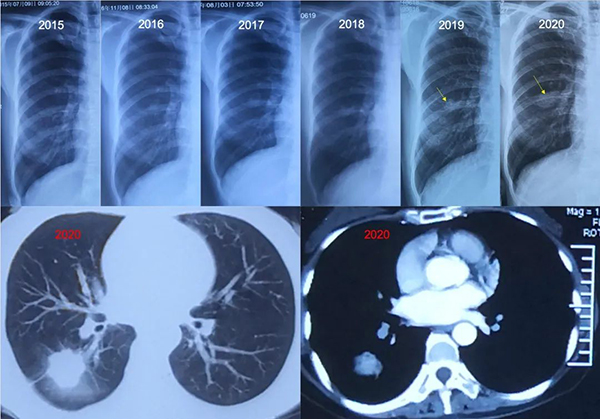

07 被胸片漏诊的典型病例

患者女性,40+岁,从2015年至今每年行胸片检查,提示“无异常”,2020年的胸片上右肺中野见一结节,复查CT发现右肺下叶背段一个3cm左右占位,边缘可见分叶、毛刺、胸膜牵拉,内部密度不均匀,增强有明显强化,是典型肺癌表现。后进行手术切除,病理为腺癌,无淋巴结转移,分期为Ib期。

根据CT结果回头看胸片,有以下几点体会:

1、如此大的病灶,生长时间可能超过10年。胸片在肺部体检时真没太大用处,小的病变看不见,大的病变看不清,胸片能看到的病变CT都能看到。因此,胸部CT是肺部检查的首选。

2、根据胸片成像质量,2015至2018年是在A医院检查,2019、2020年是在B医院检查,B医院胸片质量明显好于A医院,分辨率更高。

3、2019年已经能看出肺上有病变,但B医院无法对比之前胸片,做出了“无异常”的诊断。直到2020年该病变明显增大,提醒患者行胸部CT检查,发现了这一定时炸弹。

4、2019年至2020年,病变增大较快,提示肿瘤恶性程度比较高。

5、现在进行手术切除,可能也没有淋巴结转移,分期介于I至II期之间,但预后肯定不如更早期进行手术。